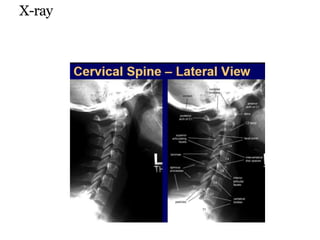

X-ray

Radiological criteria for assessing CVJ

instability

predentalspace inchildsupto 8years greaterthan 5mm,

adultsgreaterthan 3mm

open mouthviewx.ray or coronalct.........latmasses C1

displacement6mm

verticaltranslationb/w clivus and odontoid 2mm,

disruptionof ligamentousstructure